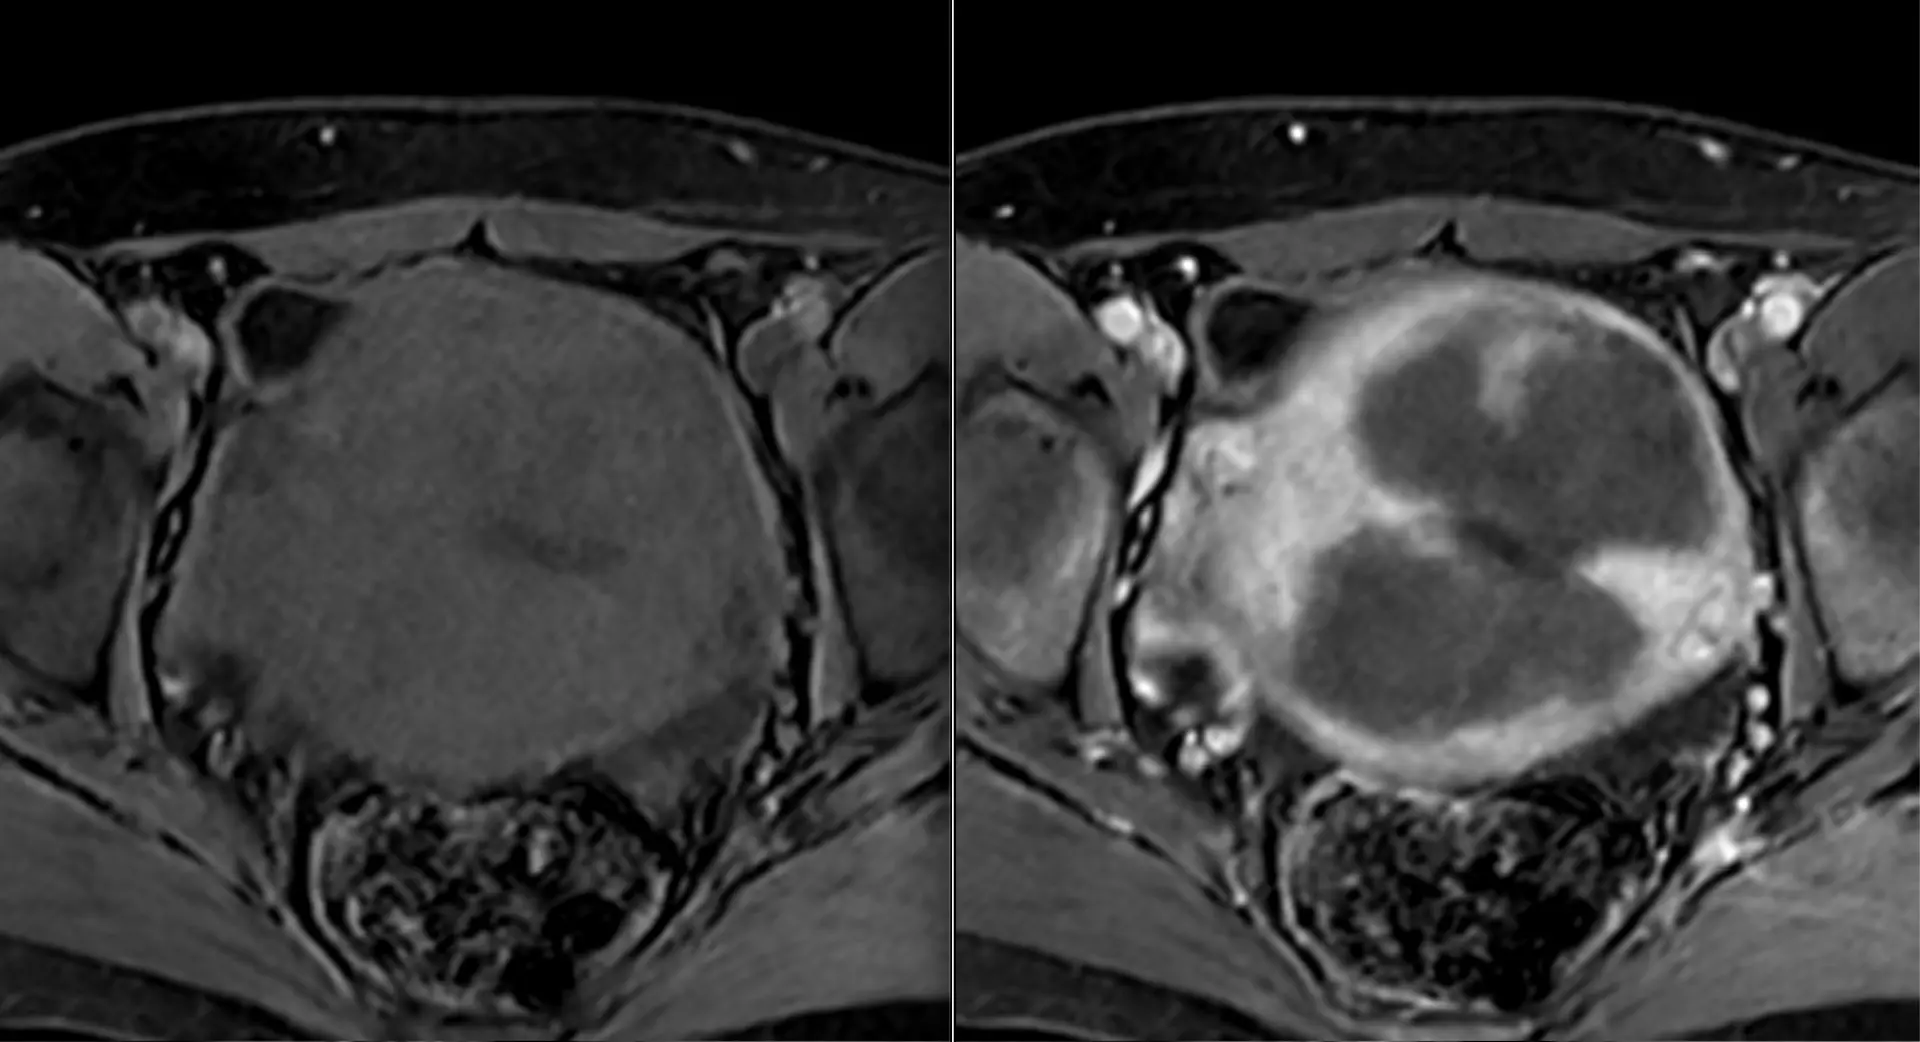

Классные тератомы. 30 лет.

В ОРАЦ есть интересный момент: когда речь о тератоме, то надо оценить, есть ли значительное количество ткани, накапливающей контраст. Субъективная вещь. Один сочтёт, что значительное, другой сочтёт, что не значительное. Но в первом случае это будет четвёртая категория и опухоли надо удалять, а во втором случае это будет вторая категория, и можно просто спокойно понаблюдать. Только что переубедил коллегу написать двойку вместо четвёрки по этим картинкам.

Кривую показываю на всякий случай, она на присвоение категории в данном случае не влияет, но дополнительно успокаивает, что ли. А зубчатость её объясняется тем, что исходные изображения и изображения после субтракции представляют собой одну серию, а вручную их разделять мне было лень. На информативность кривой это никак не влияет.

Видно, что в миометрии контраст накапливается гораздо быстрее и гораздо сильнее. То есть, если бы это на что-то влияло, то эту кривую надо было бы расценить, как кривую низкого риска.